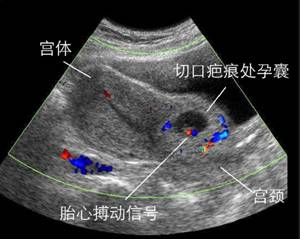

(图:疤痕妊娠)

千万谨慎疤痕妊娠

孕囊着床在子宫原疤痕处,常导致阴道大量流血以及晚期的子宫破裂,是较难处理的异常妊娠。这是剖宫产手术后再次妊娠一个严重的并发症,属于宫外孕的一种,非常凶险。如果孕早期出现先兆流产类似的腹痛出血症状,也有可能是疤痕妊娠的早期症状。一般子宫疤痕妊娠通过B超是能发现的,所以对于有过剖宫产史的女性,再次妊娠早孕时必须进行B超检查,早期发现有助于避免子宫破裂和出血,从而便于及时处理。